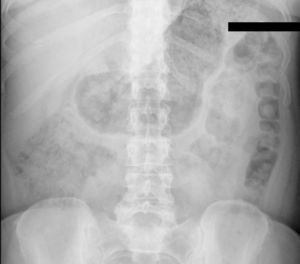

En el servicio de urgencias se realiza analítica sanguínea sin alteraciones. En la Rx de abdomen urgente se objetiva dilatación gástrica sin signos de neumoperitoneo ni oclusión intestinal (fig. 1). Se coloca sonda nasogástrica (SNG) con evacuación de 1.300ml de contenido, con franca mejoría clínica.